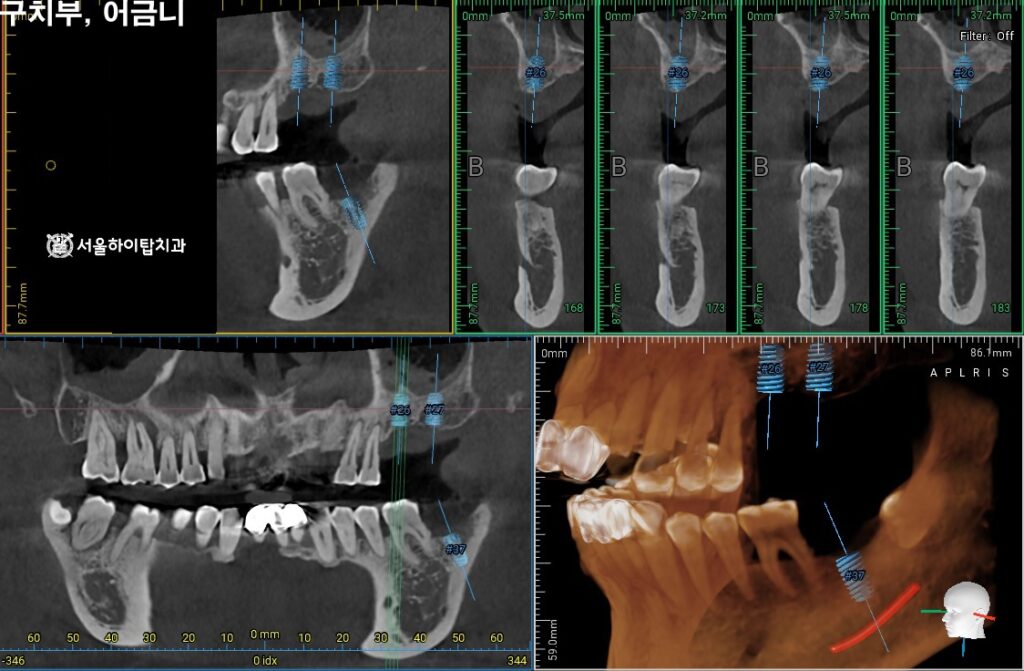

2. 정밀한 3D-CT 검진

구치부는 어금니가 상실되어 있고,

앞니의 경우 치주 지지력이 부족해

동요도가 심한 상태이므로

임플란트가 필요한 상황입니다.

이에 따라 정밀 CT 촬영을 통해

임플란트가 식립될 위치와 각도를

사전에 시뮬레이션할 수 있습니다.

이 과정에서,

치조골의 폭과 높이,

해부학 구조(상악동, 신경 등)와의 거리,

임플란트 지지력 확보를 위한 골질 상태

등을 면밀히 확인할 수 있으며,

이를 기반으로 가장 안정적이고

예측 가능한 계획을 세우게 됩니다.

현재 위턱의 경우는

골 소실이 심하기 때문에

GBR, 즉 뼈 이식이 함께

병행될 것으로 보여집니다.

이어서 앞니의 경우에도

사전 시뮬레이션을 진행하여

알맞은 위치와 각도를 결정합니다.